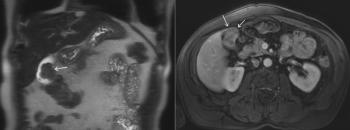

A 63-year-old man with NET metastatic to the liver undergoes MRI for evaluation of response to therapy. Based on the imaging, what is your diagnosis?